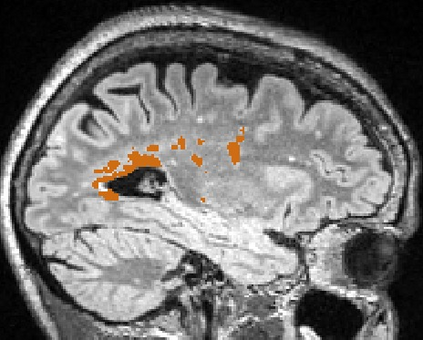

Brain atrophy and white matter hyperintensity (WMH) are critical neuroimaging features for ascertaining brain injury in cerebrovascular disease and multiple sclerosis. Automated segmentation and quantification is desirable but existing methods require high-resolution MRI with good signal-to-noise ratio (SNR). This precludes application to clinical and low-field portable MRI (pMRI) scans, thus hampering large-scale tracking of atrophy and WMH progression, especially in underserved areas where pMRI has huge potential. Here we present a method that segments white matter hyperintensity and 36 brain regions from scans of any resolution and contrast (including pMRI) without retraining. We show results on six public datasets and on a private dataset with paired high- and low-field scans (3T and 64mT), where we attain strong correlation between the WMH ($\rho$=.85) and hippocampal volumes (r=.89) estimated at both fields. Our method is publicly available as part of FreeSurfer, at: http://surfer.nmr.mgh.harvard.edu/fswiki/WMH-SynthSeg.